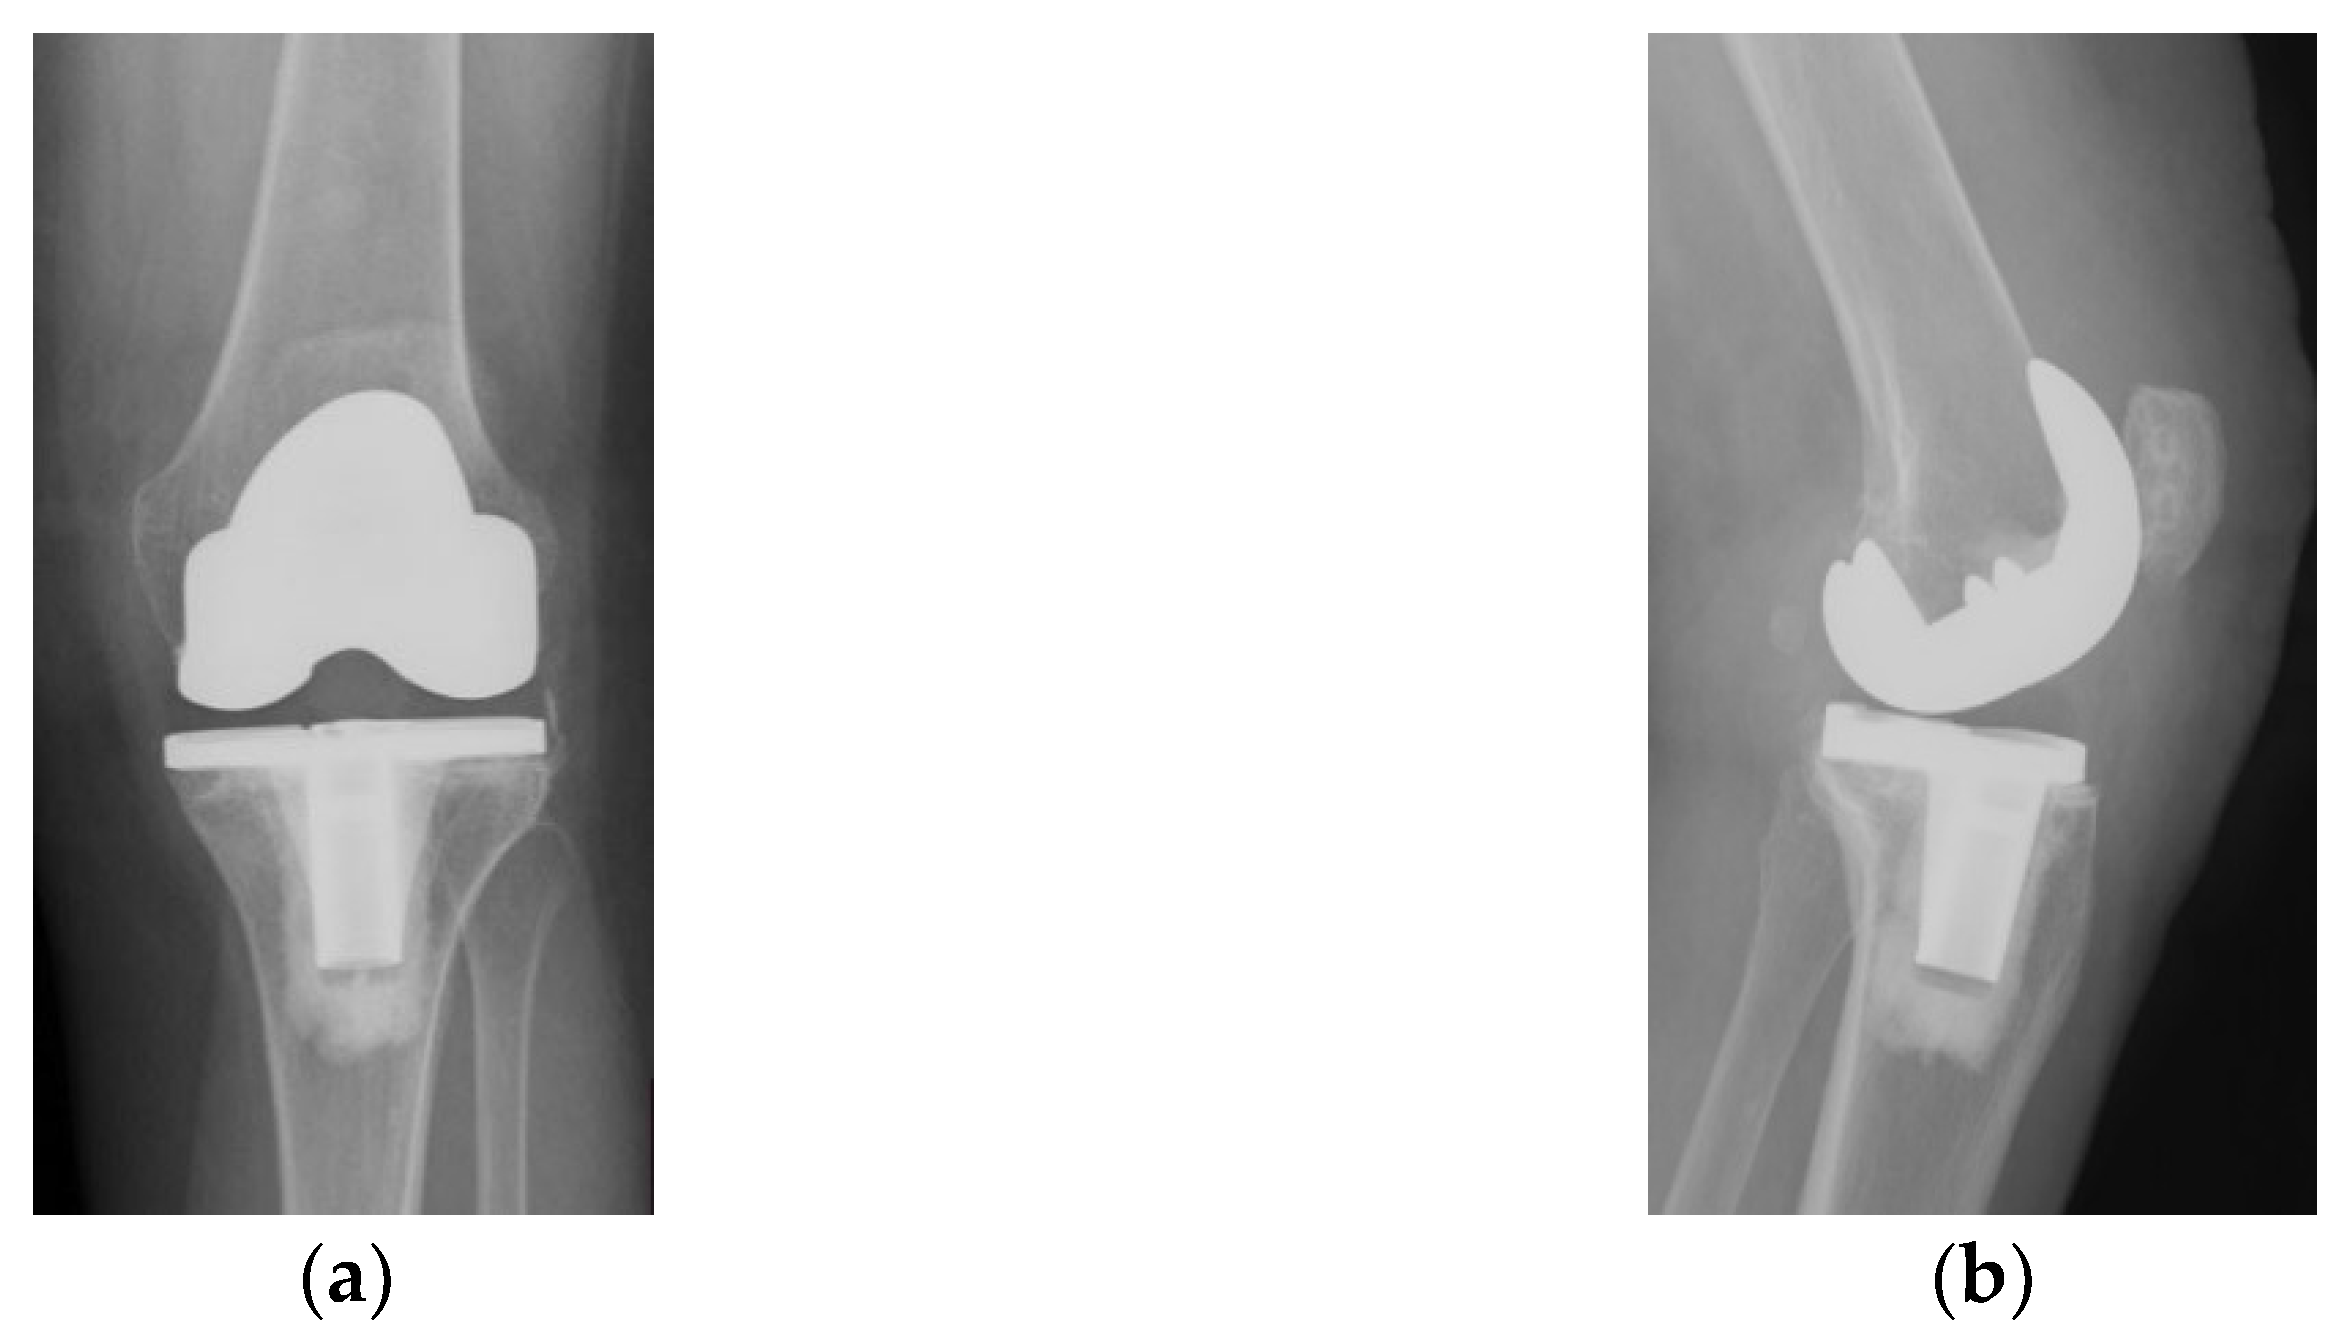

The immediate and distant postoperative evolution were favorable, as the radiological evaluation performed on the 2nd day after surgery shows; unfortunately, the lateral view is rotated (Figure 6).

Figure 6.

(a) Coronal view, patella centered on femoral axis (arrow); (b) Lateral view.

Radiological and clinical follow-up were performed at 6 weeks, 3 months and then 12 months after surgery (Figure 7, Figure 8 and Figure 9).

Figure 7.

Radiological imaging at 6 weeks after surgery: (a) Coronal view; (b) Lateral view.

Figure 8.

Radiological imaging at 3 months after surgery. (a) Coronal view, patella is centered to the femoral component (arrow); (b) lateral view.

Figure 9.

12 months after surgery: (a) coronal view, normal centered patella; (b) lateral view, no signs of patellar loosening; (c) axial view, normal centered patella in femoral trochlea.